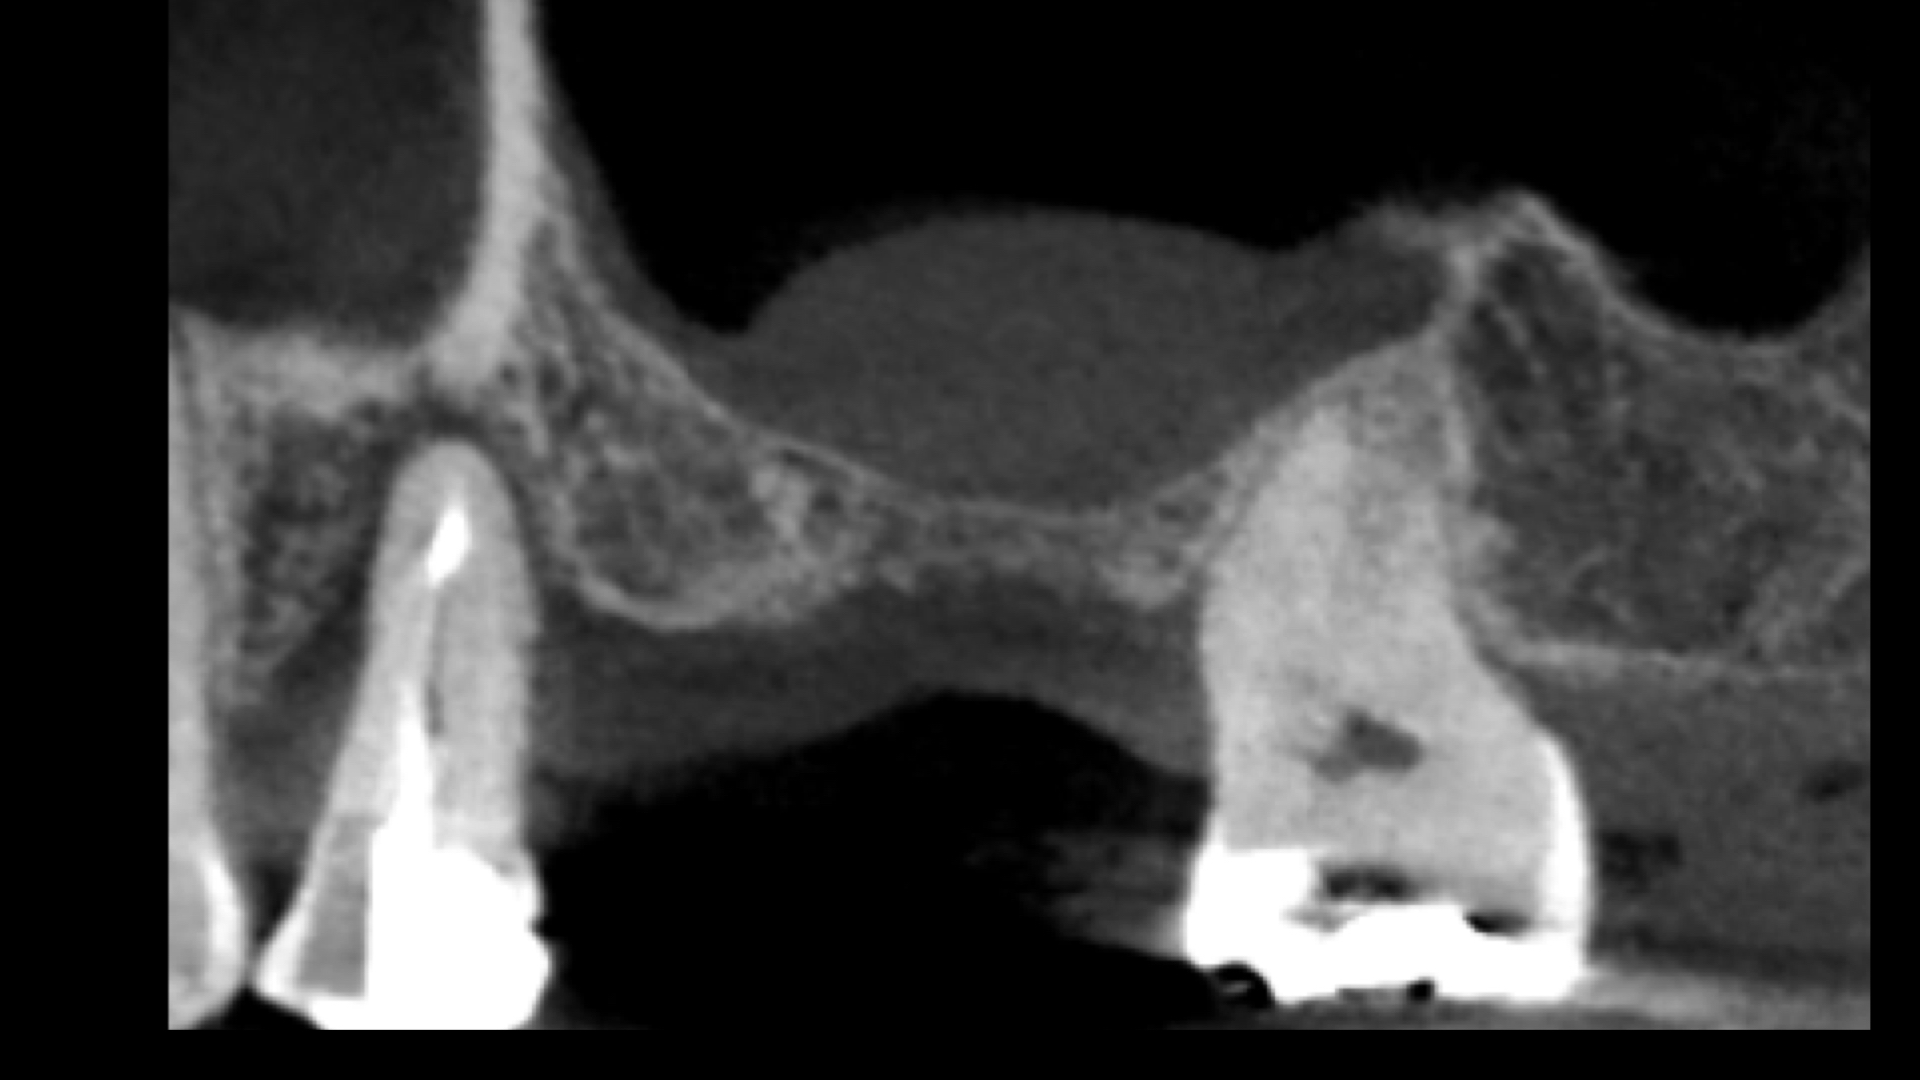

左上は支えている骨が大きく吸収しています。

CT(右の画像)上では、根尖(根の先)まで骨が吸収しており、保存することが難しい状態です。

もともと歯周病で骨が吸収していましたので、この部分にインプラントをおこなうには骨を造らなければなりません。

骨造成。またこの部分は上顎洞にも隣接しているので、上顎洞挙上術も必要です。